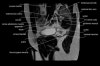

- Coronal section

T1 Allows for evaluation of both hips simultaneously even though the patient may be symptomatic in only one hip.

T2 allows for detection of abnormal fluid in both hips which may be seen in avascular necrosis, stress fractures, muscle tears or perilabral cysts.